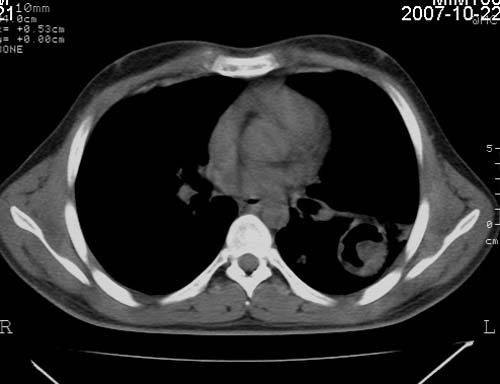

男,21岁,咳嗽、胸闷、乏力伴多汗二十余日、无明显发烧。患者一般情况好,为初三学生。

两肺肺结核,左肺空洞形成并霉菌感染?

两肺肺结核,左肺空洞形成并霉菌感染

两肺肺结核,左肺空洞形成并霉菌感染,建议痰菌检查!!